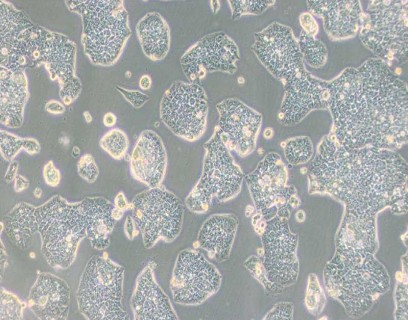

• NCI-H1944人肺癌细胞

NCI-H1944人肺癌细胞

细胞形态 : 上皮细胞样

生长特性 : 贴壁细胞